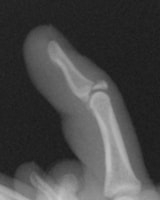

槌指(つちゆび)・マレットフィンガー

Mallet Finger

マレット変形

スワンネック変形

槌指とは木槌(マレット)のように変形した指を指す言葉であり、これには、末節骨の伸筋腱が付着する部位の裂離骨折によっておこるものと、伸筋腱の終止腱の断裂によっておこるものが含まれます。

いずれの場合も、症状はDIP関節の自動伸展障害ですが、放置するとスワンネック変形(白鳥の首様の変形)を生じます。さらに、骨折の場合には早期にDIP関節の変形性関節症を生じる原因となることがあります。

治療は、骨折があれば骨片の整復・固定を行うことで良好な結果が得られます。腱断裂の場合には2ヶ月間の外固定により4割の指に良好な結果が得られますが、6割の指には様々な程度(5〜20°)のDIP関節伸展障害が残存します。結果は、どれだけ早期に固定を開始できたか?と、どれだけしっかりとDIP関節の伸展位固定を維持できたか?にかかっており、ただ単に固定していたら治る、というものではありません。

陳旧例で骨の変形癒合がある場合には、骨切術により変形の矯正が可能です。腱断裂の陳旧例では、手術による腱の縫縮あるいは腱移行術によって変形の矯正が図られます。